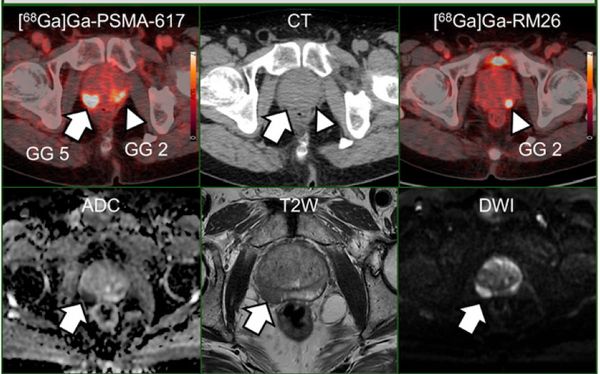

Comparative Study Shows Merits of PSMA PET/CT for Local Staging of Intermediate and High-Risk PCa